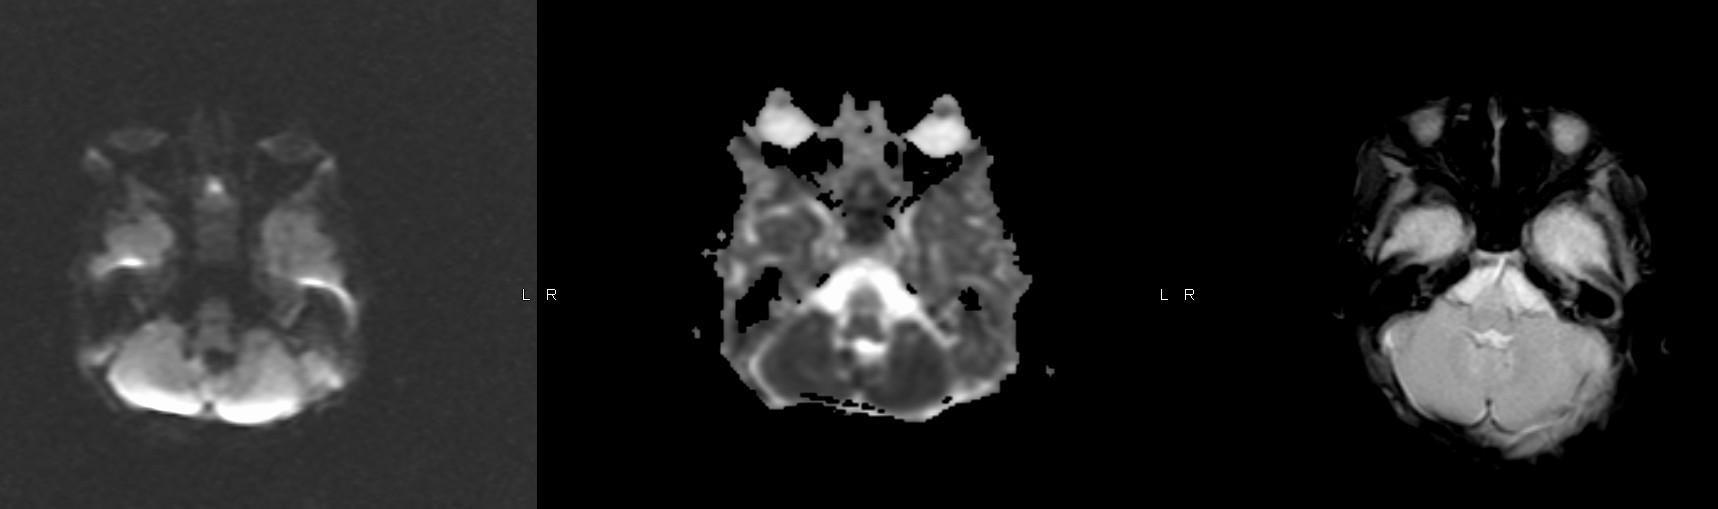

Where is the vermis? Big or small? Too small…

Do you have a normal fastigial point? Yes, pointed… What is the abnormal horizontally oriented structure? the superior cerebellar peducle…

What is the diagnosis?

What is the yellow arrow pointing to?

“molar tooth” midbrain

Large horizontally oriented superior cerebellar peduncles

Small, dysplastic vermis

“bat wing” 4th ventricle configuration

Associated with:

Absence of decussation of WM pathways in brain stem on DTI

Supratentorial:

Absent septum pellucidum

Fused fornices

Ventriculomegaly

Polymicrogyria